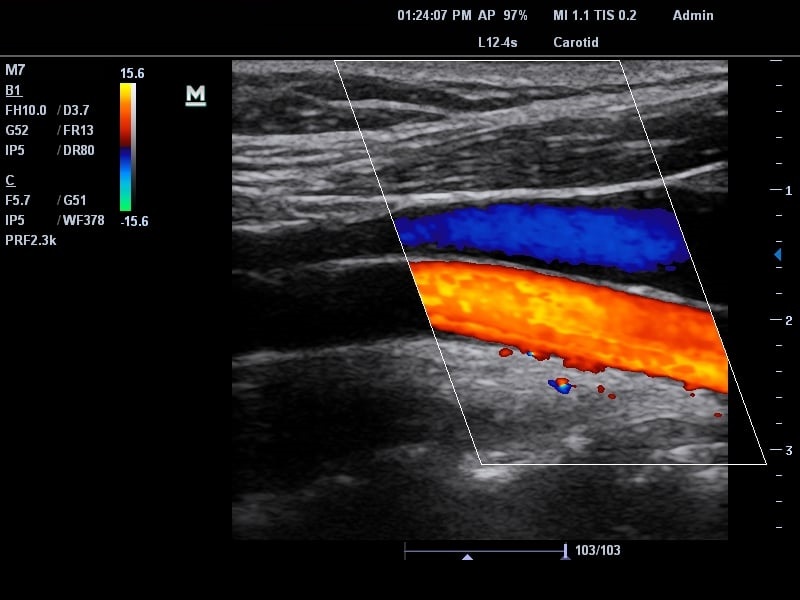

Tại các bệnh viện, hiện nay, bác sĩ có thể dựa vào hướng dẫn của siêu âm để đặt ống thông tĩnh mạch trung tâm. Biện pháp này cho phép bác sĩ xác định chính xác vị trí tĩnh mạch, giảm nguy cơ tiêm nhầm vào động mạch. Siêu âm cũng hỗ trợ đắc lực cho việc đặt kim được chính xác, đảm bảo đầu ống thông được đặt ở vị trí tối ưu.

Có thể nói, phương pháp đặt ống thông tĩnh mạch trung tâm với sự hướng dẫn của siêu âm đã giúp giảm thiểu đáng kể nguy cơ biến chứng, nâng cao cảm giác an toàn cho bệnh nhân đang điều trị.